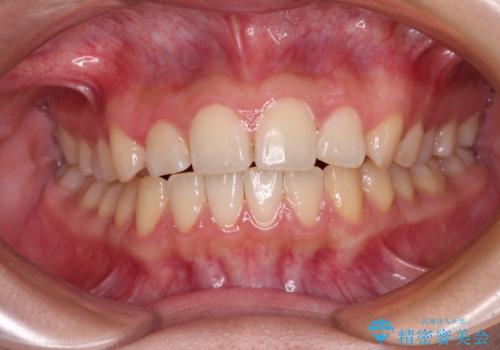

- 前歯の叢生を気にして来院された患者様です。

奥歯の咬み合わせを見ると、上顎が下顎に対して相対的に前方にあり、上下の前歯が接触していない状態でした。

咬み合わせを改善するためには、上顎臼歯を後方に移動させた咬み合わせにする必要があります。